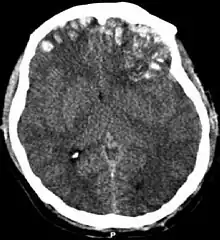

CT scan showing spread of the subdural hematoma (single arrows), midline shift (double arrows)

Systems also exist to classify TBI by its pathological features.[20] Lesions can be extra-axial, (occurring within the skull but outside of the brain) or intra-axial (occurring within the brain tissue).[24] Damage from TBI can be focal or diffuse, confined to specific areas or distributed in a more general manner, respectively.[25] However, it is common for both types of injury to exist in a given case.[25]